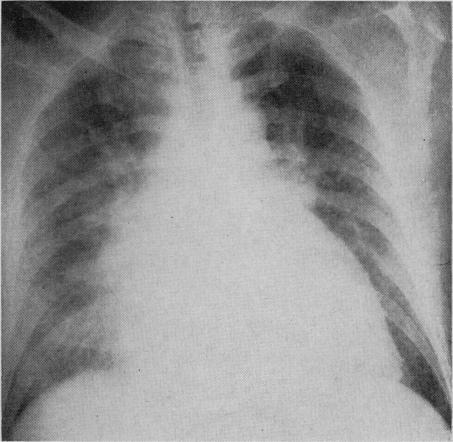

Quebec beer-drinkers' cardiomyopathy: radiological aspects.

Can Med Assoc J. 1967 Oct 7;97(15):905-9.